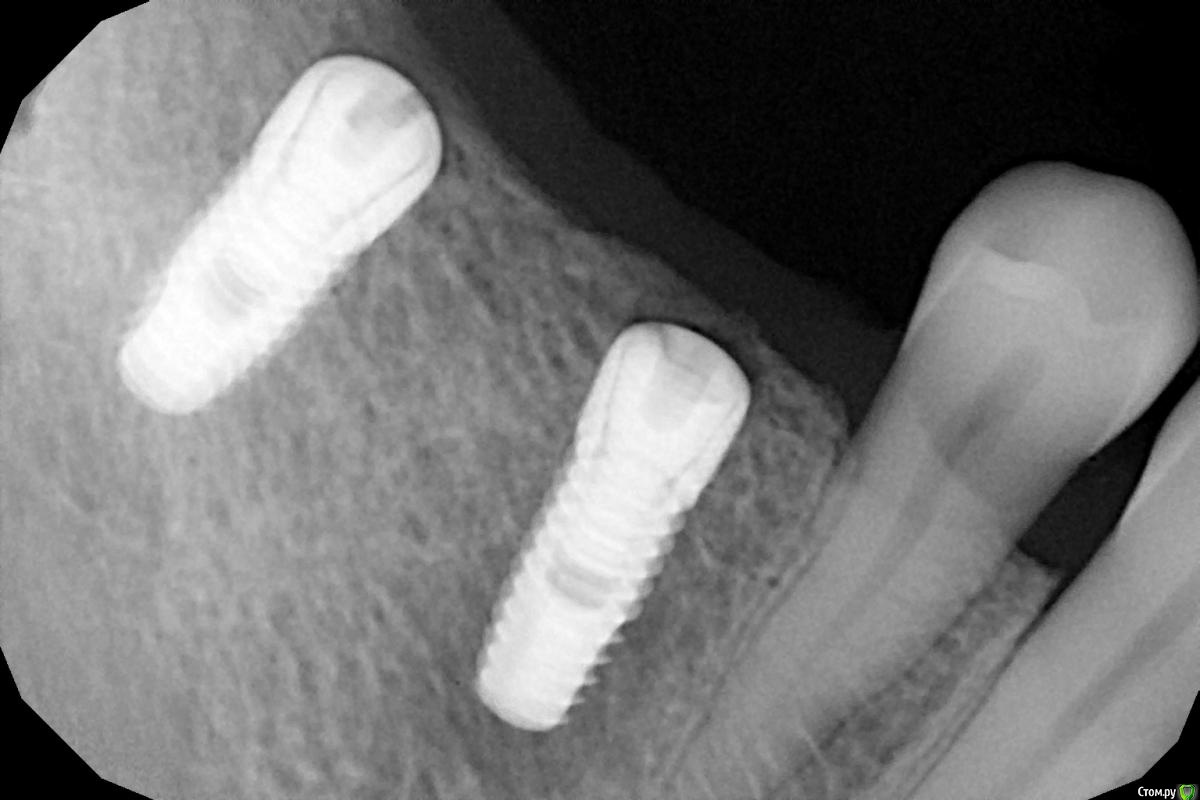

Женька Опубликовано 28 ноября, 2020 Поделиться Опубликовано 28 ноября, 2020 (изменено) Приветствую коллеги. В общем три недели назад 07.11.20 установил пациентке 2 имплантата в позиции 45-46. Гребень по ширине был около 6.5мм в области 4.5 и около 7.2мм в области 4.6 (с учётом заглубления на 1.5-2мм). Это была наверное первая имплантация во время которой я чувствовал себя спокойно и расслабленно. Всё прошло хорошо, немного покопался с непосредственным введением имплантатов, тк никак не хотели топиться на нужные 1.5мм. Поэтому пробовал методику с выкручиванием на пару витков и снова закручиванием. Особого толку не получил, потому взял финальную фрезу и чуть углублял ложе. Так несколько раз, тк боялся всё-таки немного что задену менталис и нлн. Ввиду того, что биотип у пациентки тончайший и язычно было совсем-совсем тонко - заглушки и швы. Назначил нпвс, ванны хг, аб терапию. Но на утро следующего дня пациентка сказала, что чувствует себя шикарно, решили что нпвс оставим, а аб терапию применять не будем (и грешу что в этом мою ошибка).Через неделю сняли швы, всё отлично.Спустя два дня после снятия начались какие-то "костные" боли, как говорит пациентка в области 4.5 импланта. Которые то отпускают, то снова наплывают. На 4.4 есть дефект твердых тканей (на фото виден), но судя по всему беспокоит не он .Пальпация вестибулярно в проекции 4.5 импланта болезненна, небольшая гиперемия, отёка нет. Гигиену пациентка запустила, тк боялась туда залезать и чистить. Снимки прилагаю первые два от 07.11, два последующих 28.11. Ну и внутри ротовые день операции и сегодняшние числа.Похоже 4.5 на выход? своими "туда-сюда" наверняка я нагрел всё что можно... снова расстройство в той работе, где накосячить предельно сложно... Добавка: пить аб ведь сейчас уже бесполезно? Изменено 28 ноября, 2020 пользователем Женька Ссылка на комментарий

Женька Опубликовано 28 ноября, 2020 Автор Поделиться Опубликовано 28 ноября, 2020 (изменено) Какой торк получили?45Вы тоже видите заглушки светят? Изменено 28 ноября, 2020 пользователем Женька Ссылка на комментарий

колесников Опубликовано 28 ноября, 2020 Поделиться Опубликовано 28 ноября, 2020 (изменено) Имплант 13 мм? Зачем? При планировании видно, что он упирается апексом в кортикалку. По этому и поставить не могли сразу. Торк 45. Если имплант плотно контактирует с компактной пластинкой,она резорбируется окончато,со всеми вытекающими. Стоило выбрать имплант 8.5мм. Если притопили имплант,зачем поставили заглушку? Имплант зарастёт придётся выпиливать ,откапывать заглушку,ломать то что наросло непосильным трудом. Хороший торк-ставьте рабочий фдм. Сомнения-мелкий фдм или заглушка +1. Рекомендую сделать контрольный кт и поставить фдм Изменено 28 ноября, 2020 пользователем колесников 5 Ссылка на комментарий

Женька Опубликовано 29 ноября, 2020 Автор Поделиться Опубликовано 29 ноября, 2020 Я бы сейчас сделала три вещи :дала курс антибиотика шикарной женщине,гигиену навела бы во рту или хотя бы в этой области,депульпировала премоляр.Чтобы прикрыться со всех сторон. Выждать. Вынуть всегда успеется.А потом.. может,там уже формики просятся?Три недели, не рановато ли? По поводу премоляра, терапевта напрягу. А на каком режиме Вы закручиваете/выкручиваете?20оборотов на торке 30, далее руками динамометрическим ключом. Имплант 13 мм? Зачем? При планировании видно, что он упирается апексом в кортикалку. По этому и поставить не могли сразу. Торк 45. Если имплант плотно контактирует с компактной пластинкой,она резорбируется окончато,со всеми вытекающими. Стоило выбрать имплант 8.5мм.Импланты 10мм каждый, разметка на планировании - глубина препарирования с учётом заглубления. Проблема то как раз в области 4.5 импланта, там нет такого контакта с кортикой апикально, а область шейки хорошо развальцевал кортикальной фрезой. 4.6 где как раз контакт кортикальный спокоен. Если притопили имплант,зачем поставили заглушку? чтобы избежать проблем как в предыдущем моём случае, где тоже было тонко язычно. Потому хотел на этапе раскрытия работать с десной и язычно перемещать объём. http://forum.stom.ru/topic/40254-otsrochennaia-implantatciia/ Сомнения-мелкий фдм или заглушка +1. что значит заглушка +1? Если сейчас залезть и выкрутить заглушки не велики ли риски прокручивания имплантата...ведь на 3-5 недели самая большая потеря первичной стабильности происходит. Ссылка на комментарий